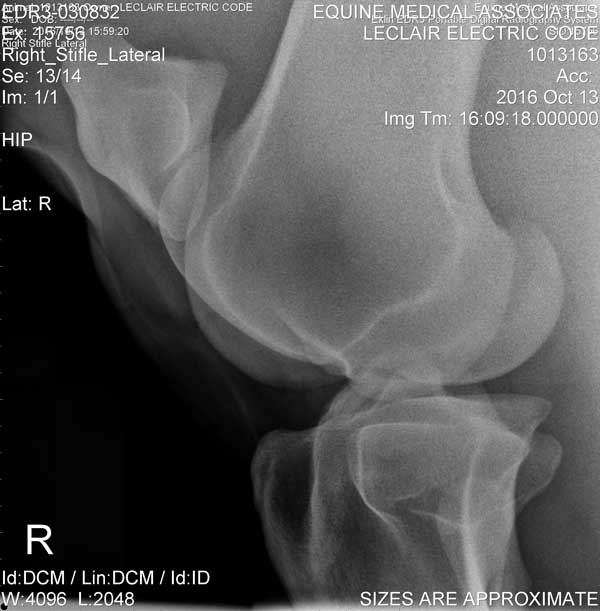

Electric Code is 11 years old at the time these X-Rays were taken on October 13, 2016

Stifle